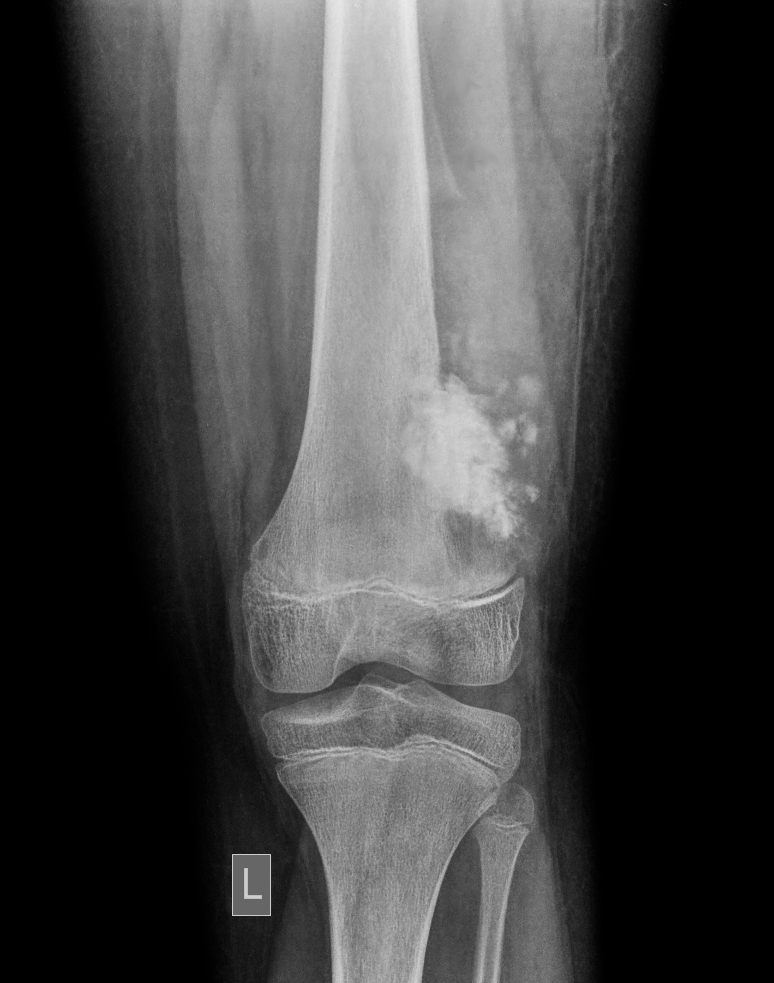

Vous vous occupez de Mathéo, 15 ans, hospitalisé dans votre service depuis ce matin pour exploration d’une masse fémorale douloureuse avec boiterie depuis 3 mois.

Votre examen clinique est normal en dehors d’une masse douloureuse à la palpation de l’extrémité inférieure du fémur gauche.

Vous faites réaliser une imagerie que voici.